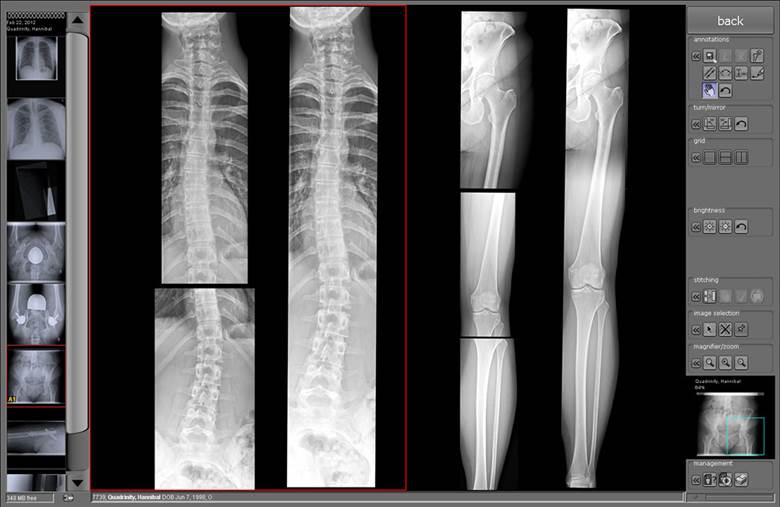

- Tích hợp phần mềm đồng bộ cho phép điều khiển chụp, thu nhận và xử lý hình ảnh cho toàn bộ các bộ phận: Sọ não, ngực, bụng, chậu và các chi

- Chức năng tự động: Tự động nối hình, tự động đồng bộ dịch chuyển giữa bóng X quang và Bucky của Giá chụp phổi và Bàn bệnh nhân